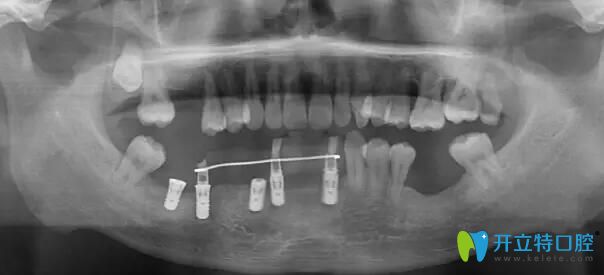

南通摩爾口腔牙齒種植前檢查

通過術(shù)后CT 對(duì)比檢查,與術(shù)前設(shè)計(jì)幾乎完全一致,實(shí)現(xiàn)種植前的設(shè)計(jì)方案。